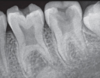

which type of dentin dysplasia is this?

type 1

note rootless teeth on radiograph, normal enamel and coronal dentin, and shortened radicular dentin